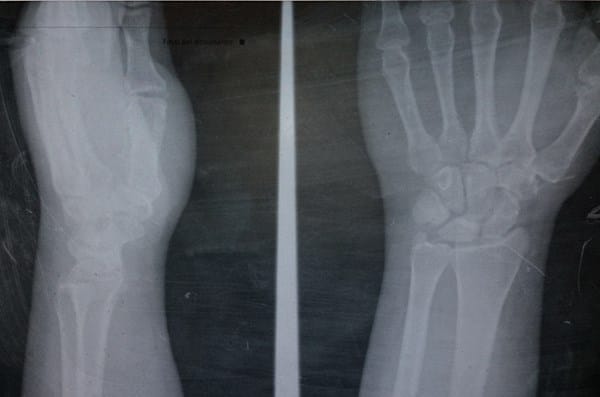

Hace 2 meses me resbalé y caí sentando y caí sobre mi muñeca izquierda, pensé que el dolor se me quitaría con los días pero a veces mejora y luego me molesta al doblar la muñeca.

Aquí la Radiografía!